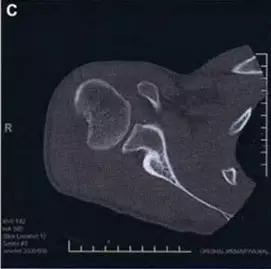

1. Hill-Sachs 损伤和反 Hill-Sachs 损伤

肩关节脱位时,肱骨头和关节盂发生撞击,肱骨头表面凹陷性骨折。

肩关节前脱位时发生的肱骨头后外侧凹陷性骨折,是经典的 Hill-Sachs 损伤(Hill-Sachs lesion);

而肩关节后脱位时发生的肱骨头前内侧凹陷性骨折,是反 Hill-Sachs 损伤(Reverse Hill-Sachs lesion/ McLaughlin lesion)。

Hill-Sachs 损伤的 CT 片 (来源:Hill-Sachs Injuries of the Shoulder)